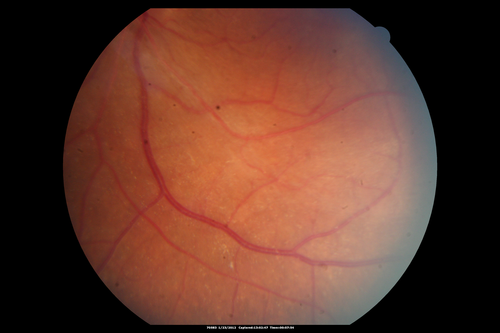

Retinitis Pigmentosa Sine Pigmento or Unknown Dystrophy - Peripheral Superficial White Spots and Recurrent CME

46-year-old woman three of her 5 siblings have been diagnosed with retinitis pigmentosa.  Her mother and father were seen and as far as everyone can tell, neither of them has it, although there was some thought they might be carriers.  They were evaluated twenty five years ago and since then as far as she knows, there has not been a lot of testing done.

She has noticed a substantial decline in vision in both eyes over the last month or two.   OD 20/40,  OS 20/50.   IOP:  Both eyes have CME